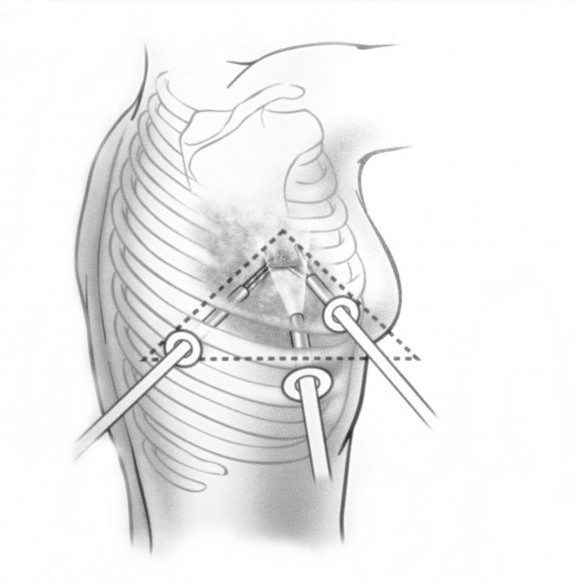

При невозможности получить образец ткани для исследования эндоскопически применяются инвазивные методы: трансторакальная биопсия, медиастиноскопия, видеоторакосокпия. Последние два метода — это серьезные операции, которые проводятся в специализированных медицинских учреждениях.